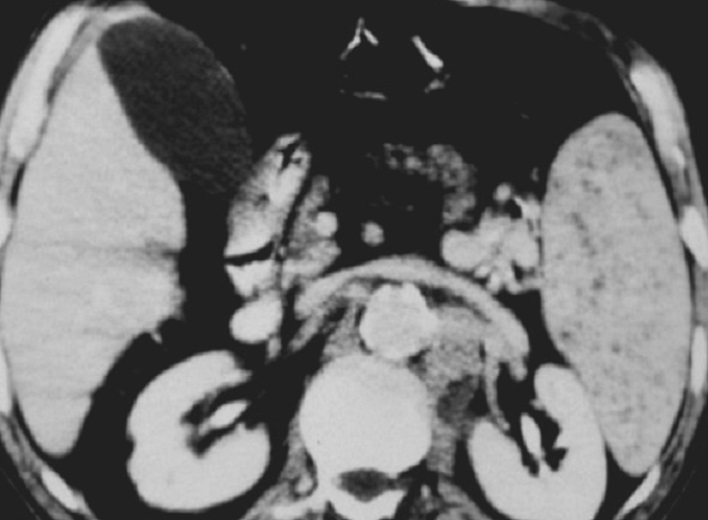

La lesion de abces fungique se presence

au rate sous forme des micro-abces arrondie ou

ovalaire hypodensite diffusant . Ces lesions peuvent

en s.observent encore dans le foie . Image

radiologique TDM plus C+ intraveineuse , coupe

axiale |

Aspect radiologique en oeil

de boeuf de type II de abces fungique de la

rate ( fleche rouge ) . La lesion peut en

s.observe dans le foie droit . Coupe TDM axiale avec

injection de contrast intraveineuse . |